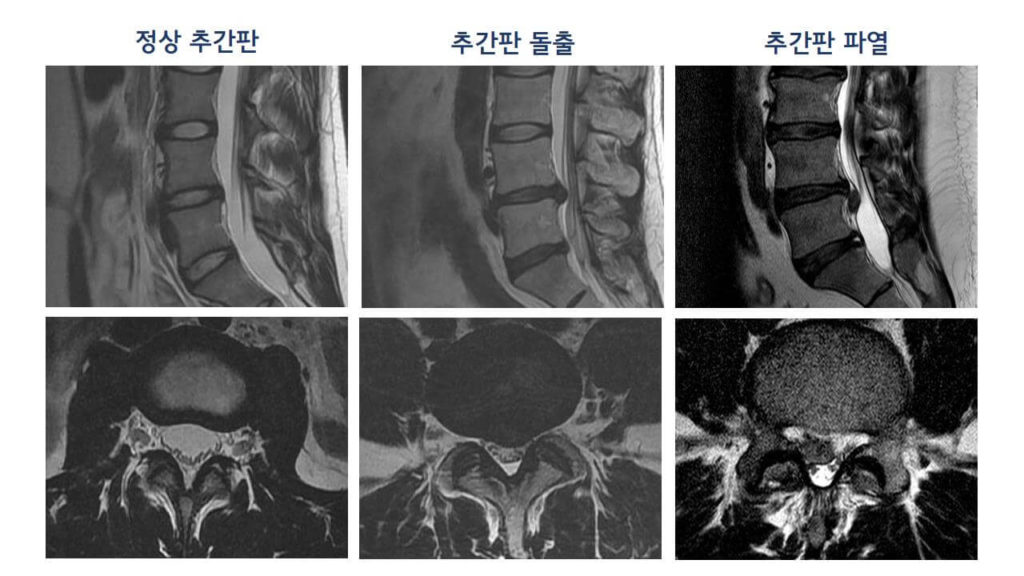

허리디스크에 대해 아직 살펴보지 못하셨다면 허리디스크가 어느 부위를 말하는지 확인하시고 시기에 맞추어 운동하여 주십시요.